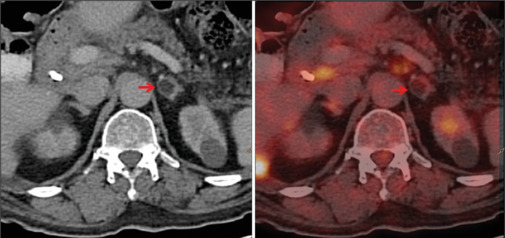

Detection of adrenal lesions either incidentally, or in symptomatic cases and/or during staging/restaging of oncological cases, it is very crucial to know the adrenal lesion is benign or malignant. Fluorodeoxyglucose positron emission tomography-computed tomography (FDG PET/CT) helps in this comprehensive evaluating process. Here, we present the most frequently facing adrenal lesions in routine oncological PET/CT scans. The aim of this presentation is to know the FDG uptake spectrum of various adrenal lesions on PET/CT scan so that increase the diagnostic accuracy and spectrum of differential diagnosis.

Abstract Image